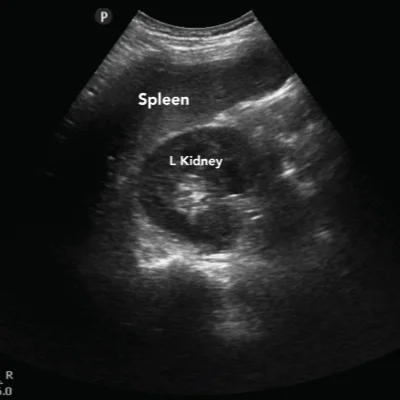

General Ultrasound

Our general ultrasound scans help visualize major organs and soft tissues, including

Abdomen

Liver, gallbladder, pancreas, kidneys, spleen

These scans are commonly used for abdominal pain, swelling, or abnormal lab results. They are quick, non-invasive, and require minimal preparation.